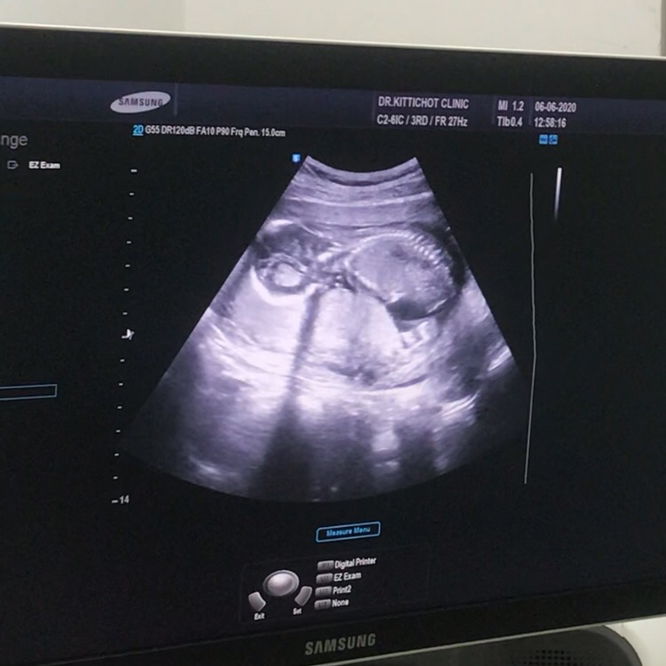

อายุครรภ์ 17 week หมอบอกว่า น้ำหนัก 400 กรัม ขนานนี้เล็กหรือใหญ่หรือพอดีครับ

คือตอนนี้เมียผมอายุครรภ์ 17 week หมอบอกว่าน้ำหนักลูก 400 กรัม แล้วมีคนบอกว่าเด็กใหญ่เกินเกณฑ์จริงไหมครับ แล้วถ้าเด็กใหญ่เกินเกณฑ์จะมีภาวะเสี่ยงครรภ์มีพิษ จริงหรือไม่ครับ